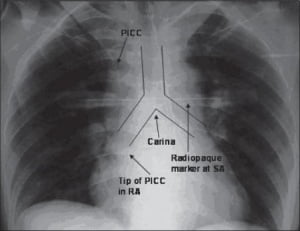

Su validación se basa sobre la interpretación de la posición del catéter gracias a unas referencias anatómicas no claramente visibles en la imagen.

Con este método no se ve la unión cavo-auricular y, por lo tanto, es subjetiva.

Esto se muestra en el estudio “Optimizing the patient positioning for PICC line tip determination” (Harako ME1, Nguyen TH, Cohen AJ), en el que se prueba que existe una diferencia de interpretación de una placa de posición de un acceso vascular cuando distintos profesionales la analizan.

La longitud de la Vena Cava Superior puede variar bastante de un paciente a otro: entre 4,4 y 10 cm. Y esta es solo una de las estructuras anatómicas que varían de un paciente a otro, entre otras muchas.

Por todas estas razones, la placa es un método totalmente desaconsejado por las recomendaciones internacionales (INS, GAVeCeLT).